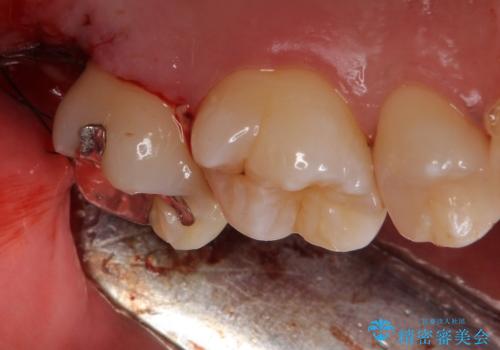

- 銀の詰め物のやり替えを主訴に来院されました。

歯の奥が歯ぐきに埋もれている状態であったため、埋まっている親知らずを抜歯しつつ歯茎の高さを落とし、外れにくいジルコニアクラウンを装着していきます。